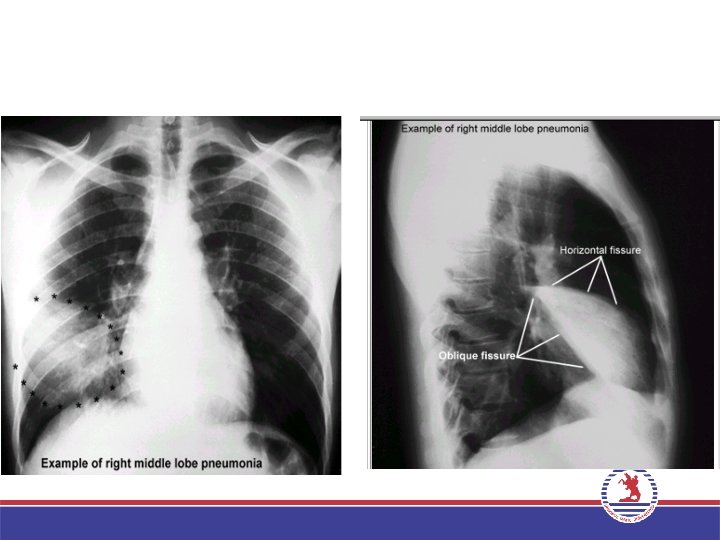

TANI: Anamnez, fiziksel değerlendirme, göğüs filmi, kan kültürü, balgam muayenesi, gerekirse bronkoskopi ile tanı konur.

• Anatomik Dağılıma Göre Sınıflandırma a)Bronkopnömoni b)Segment Pnömonisi c)İnhalasyon Pnömonisi d)Aspirasyon Pnömonisi e)Lober Pnömoni